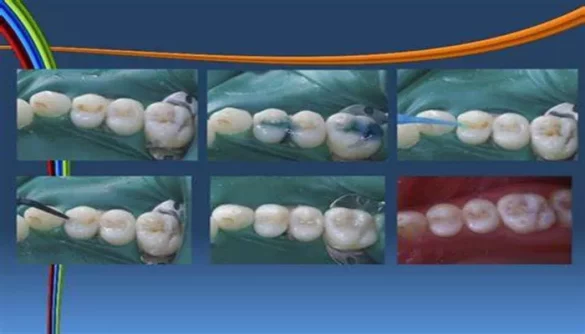

A composite filling is a tooth-colored material used to fill cavities caused by decay. It is made from a blend of resin and glass particles, which allows it to resemble the natural color of teeth. Composite fillings are widely used for their aesthetic appeal, as they blend seamlessly with the natural tooth structure. They are commonly used in front teeth or any visible areas where traditional metal fillings would be noticeable.

The process of getting a composite filling involves your dentist removing the decayed portion of the tooth and filling it with the composite material. The filling is then hardened using a special light.